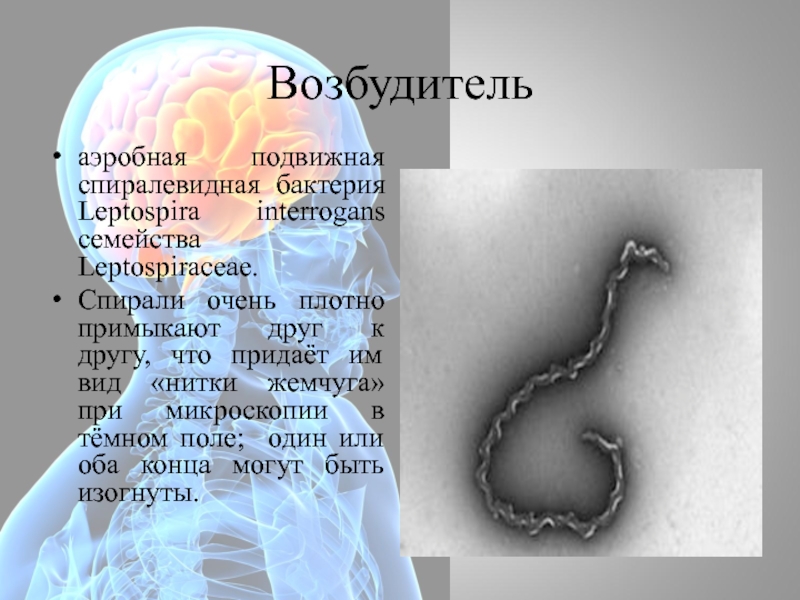

Лептоспиры: фотографии удивительных микроорганизмов